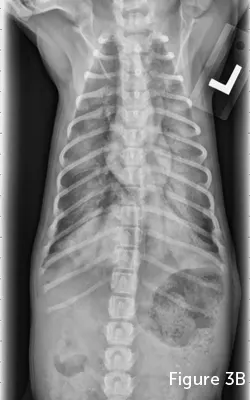

FIGURE 3

Lateral (A) and VD (B) thoracic radiographic views of a dog with NCPE. Note the focal interstitial to alveolar pattern present in the 3 caudodorsal lung fields.

Diagnosis of NCPE is often based on history, examination, and radiographic imaging. Classic radiographic findings include increased interstitial or alveolar opacity, notably in the caudodorsal lung fields (Figure 3). This contrasts with radiographic findings in patients with cardiogenic pulmonary edema, notably perihilar edema. However, other forms of respiratory disease should be investigated, including cardiogenic pulmonary edema, pneumonia, and hemorrhage from trauma or coagulation abnormalities. Echocardiography can exclude cardiogenic edema and left-sided heart failure. A coagulation profile should be performed and pneumonia ruled out based on history, physical examination findings (eg, nonfebrile), and CBC results.